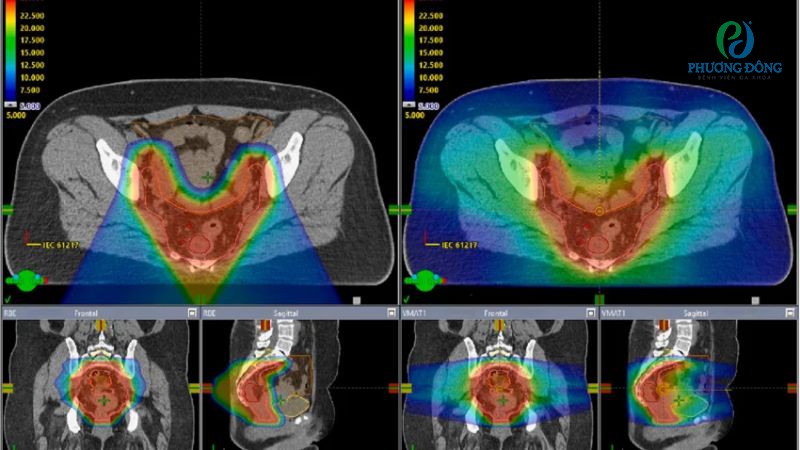

Trong điều trị ung thư trực tràng, VMAT hoạt động bằng cách đưa liều bức xạ tối đa trực tiếp đến khối u ác tính, đồng thời giảm thiểu tổn thương cho các mô lành xung quanh như hậu môn, đại trực tràng. Khi máy quay quanh cơ thể, hình dạng và cường độ của chùm tia xạ được điều chỉnh liên tục để nhắm trúng đích.

- Bước 3: Lập kế hoạch xạ trị dựa trên kết quả chụp hình ảnh, kỹ thuật viên, bác sĩ ung bướu sẽ làm việc với nhau để tính toán chính xác liều lượng, hướng tia và thời gian chiếu xạ tối ưu.